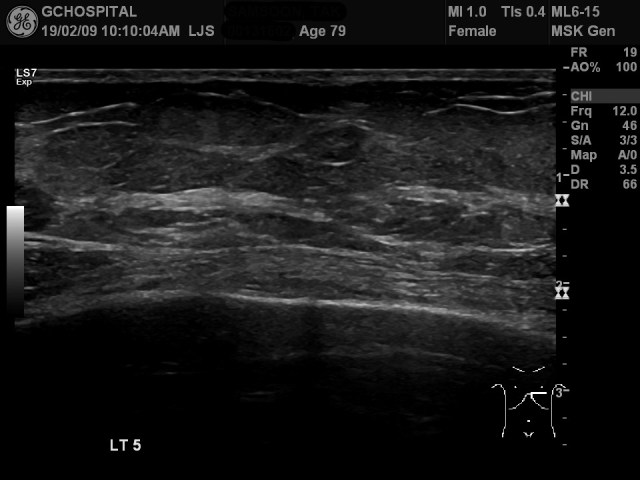

왼쪽 5번째 늑골에서는 더 뚜렷하게 bone cortex가 끊어져 있으며, subperiosteal hemorrhage의 양도 네번째 늑골보다 더 많습니다. scaleneus anterior muscle이 출혈에 의해 벌어져서 위로 밀려나있는 양상도 더 뚜렷하게 보입니다.